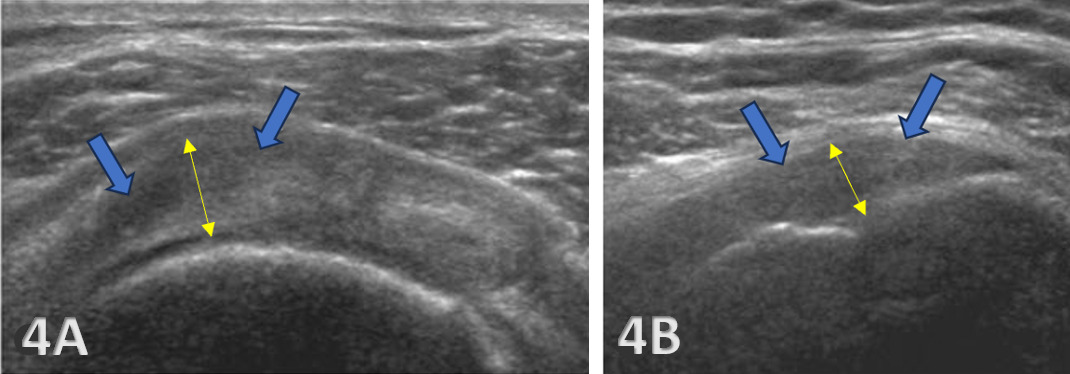

Transverse Scans: Begin with transverse scans to identify the spine of the scapula and follow the muscle belly towards its insertion on the humerus. The transducer is transversely placed inferiorly and slightly laterally from the scapular spine. Passive internal and external rotation of the patient’s arm may be helpful in visualization of the tendon. The infraspinatus tendon appears as a beak-shaped soft-tissue structure that progressively thins as it approaches its attachment to the posterior aspect of the greater tuberosity.6 Additional structures seen at this level are the posterior glenoid labrum, imaged as a hyperechoic triangular structure and the hypoechoic articular cartilage of the humerus.

Ultrasound imaging of the infraspinatus must be carefully interpreted. Normal anatomy appears as a fibrillar pattern with uniform echotexture. Pathological findings may include:

Tendinopathy: Characterized by hypoechoic (darker) areas and tendon thickening which may signify tendinopathy or degeneration.

Tears: Full-thickness or partial-thickness tears are displayed as hypoechoic or anechoic (absence of echoes) defects within the tendon. Additionally, they may be identified by discontinuities in the tendon fibers.